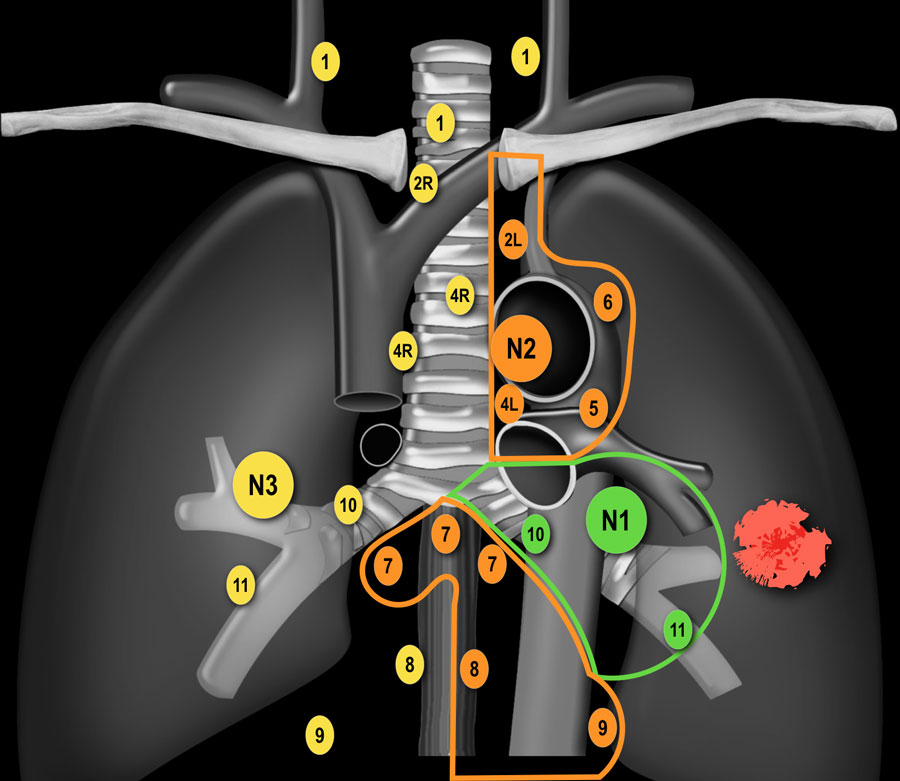

N-стадирование Классификация регионарных лимфатических узлов IASLC 2009 г.

Граница между лимфатическими узлами 10 и 4 группы находится на правой нижней границе непарной вены и на левой верхней границе легочной артерии (отличие N1 и N2 стадий). Достаточно важно разделять лимфатические узлы 1-ой группы и 2/3-ей групп

(отличие N3 и N2 стадий). Граница между группами лимфатических 4R и 4L является левый латеральный контур трахеи, а не срединная линия. Паракардиальные, лимфатические узлы молочных желез, диафрагмальные,

межреберные и подмышечные лимфатические узлы не входят в карту

лимфатических узлов согласно IALSC, несмотря на то, что они редко, но

могут вовлекаться в патологический процесс. ПЭТ/КТ является методом выбора при определении N-статуса. |

N2 - стадия На данном снимке N2-стадия у пациента с ипсилатеральной медиастинальной

или субкаринной лимфаденопатией. |

N3 - стадия При N3-стадии визуализируют контралатеральную медиастинальную или контралатеральной хиларную лимфаденопатию или лимфааденопатию надключичных узлов. Считается нерезектабельным состоянием. |

|

На снимках представлены два пациента с раком легких и лимфаденопатией на

стороне поражения и контралатеральной стороне. |

N3-стадия При N3-стадии визуализируют контралатеральную медиастинальную или контралатеральной хиларную лимфаденопатию или лимфааденопатию надключичных узлов. Считается нерезектабельным состоянием. |

N-стадия левое легкое